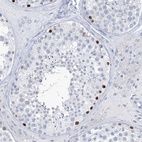

Immunohistochemical staining of human testis shows strong nuclear positivity in cells in seminiferous ducts.